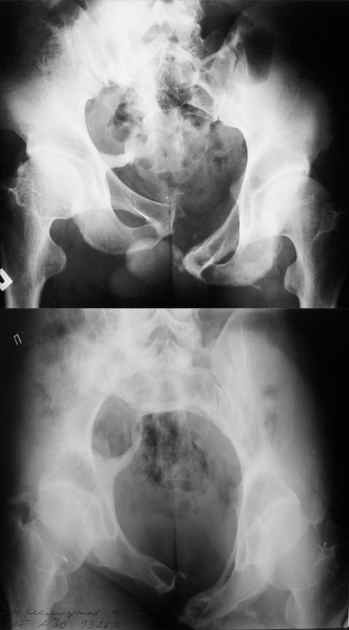

Дорогой Андрей. Мы имеем дело с комбинированной (ротационно и вертикально) нестабильностью таза со смещением правого гнемипелвиса. При таких переломах, фиксация только переднего полукольца вне зависимости от метода фиксации, как уже было сказано Djoldas Kuldjanov, M.D., не может создать адекватной фиксации. И перелом пластины был вполне ожидаемым после активизации пациента. Смещение сохраняется, и по-видимому не 2 см., а все 4, если не более. Разница всего (+2 см) по конечностям как вы указываете, скорее скомпенсировано позвоночником и протезом. Дополнительные снимки или КТ исследование помогли бы уточнить степень смещения с точностью до мм., выявить перелом поперечного отростка пятого поясничного позвонка, или помимо разрыва правого крестцово-подвздошного сочленения выявить перелом боковой массы крестца справа и т.д. При возможности, конечно, все это желательно сделать. Но мало что изменится с практической точки зрения, т.к. задача - это низведение репозиция и надежная фиксация правого гемипелвиса. Учитывая плачевный опыт стержневого аппарата, давность травмы совершенно очевидно, что поставленная задача достижима при открытой репозиции и одномоментной фиксации переднего полукольца с артродезированием правого крестцово-подвздошного сустава. Операция выполняется в положении больного на здоровом боку или полубоку из расширенного трансоссального подвздошно-пахового доступа с переходом на лонное сочленение доступом по Pfannenstiel. Указанный доступ обеспечивает подход к крестцово-подвздошному сочленению как спереди так и сзади. После артродезирования выполняется синтез лонного сочленения. Клинический пример

Пациентка С.26 лет. Травма за 6 месяцев до поступления

Укорочение правой нижней конечности до 10см

23.09.2003. Одновременный остеосинтез переднего и заднего тазовых полуколец

Результат через 10 дней

и 8месяцев после операции

Это наблюдение 5-летней давности тогда кровопотеря составила 2,5 литра. В настоящий момент мы теряем не более 0,7-1,5 литров при одностороннем повреждении и около 2,5-3 литров тогда, когда речь идет о двусторонних повреждениях. Клинический пример.